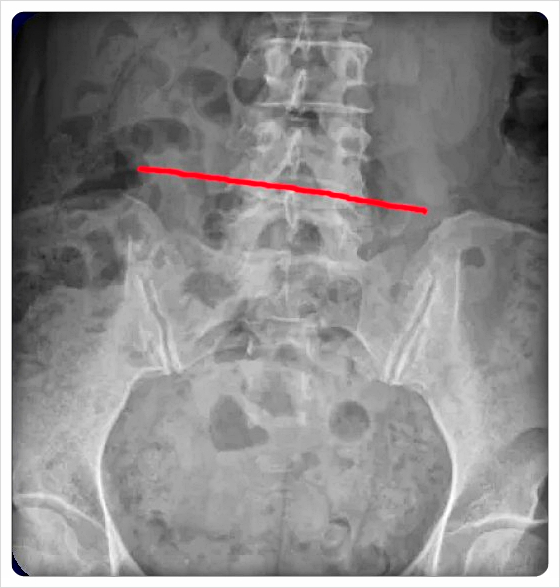

업슬립은 골반 뼈 한쪽이 위로 올라간 상태를 말합니다.

오래 서 있거나 한쪽 다리를 꼬고 앉는 습관이 많을수록 생기기 쉬운 변형입니다.

업슬립이 반복되면 허리 주변 근육이 과도하게 긴장해 통증이 악화될 수도 있습니다.